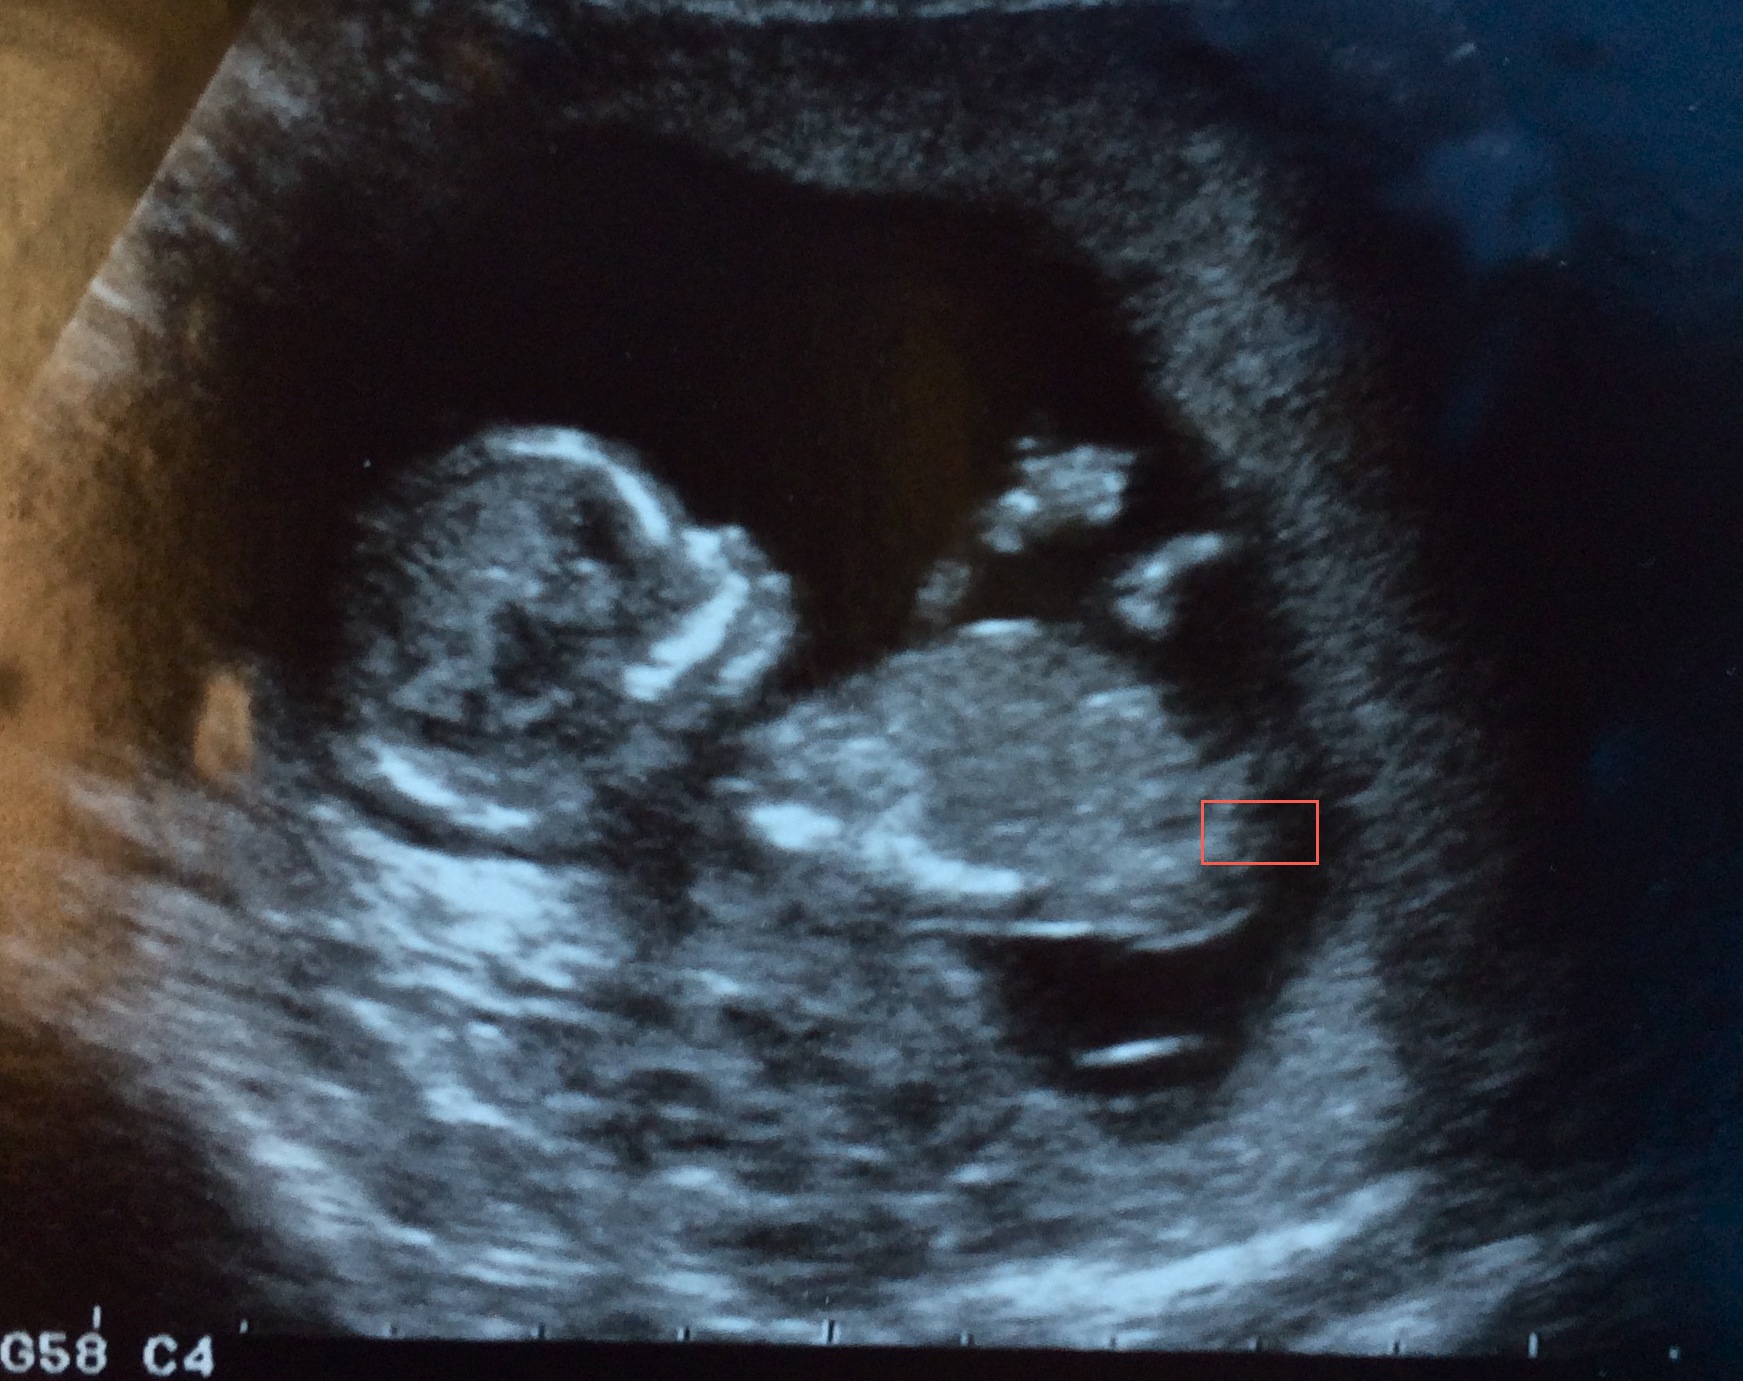

I don't see a clear nub in my 12 week ultrasound but I think I see something?! It's driving me crazy! Guesses please?

Thanks for your guesses ladies! I am due July 1st :) My mind is playing tricks on me in this photo... one minute I think I see a nub pointing up (although this could definitely be a leg!) and the next I can see a clear parallel fork (as I've highlighted in the box below... hard to see unless blown up!). Attachment 22865

Yep I see the fork!! Can't tell for sure if that's the nub though... Fx

nub isnt shown. That "fork" is just distortion.